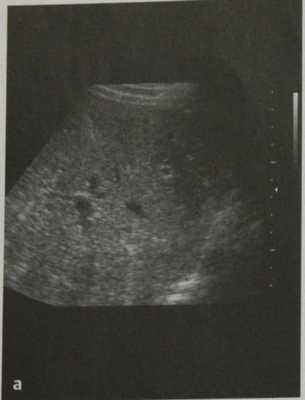

(Левый) Серошкальный ультразвуковой срез печени. Отмечается неоднородность эхоструктуры паренхимы печени, вызванная множественными гамартомами печени, слишком маленькими для того, чтобы их выделить. Другие мелкие, кистозные образования представляют собой гамартомы чуть большего размера, внутреннее кистозное строение которых может быть визуализировано.

(Правый) Цветовая допплерография подтверждает, что у этого пациента с множественными гамартомами печени отсутствует васкуляризация их кистозного содержимого. (Левый) КТ с контрастированием у этого же пациента, аксиальная проекция. Визуализируются множественные крошечные гамартомы печени низкой плотности, хаотично расположенные по всей паренхиме печени.

a) УЗИ. Негомогенное изображение с мелкими трудноопределяемыми гипоэхогенными очагами.

b) КТ после введения контраста. Множественные мелкие очаги пониженной плотности, не накапливающие контраст.

c) МРТ после введения контраста. Множественные мелкие гипоинтенсивные очаги, не накапливающие контраст.

d) МР-изображение в режиме НАSТЕ. Множественные гиперинтенсивные очаги с кистозным компонентом.